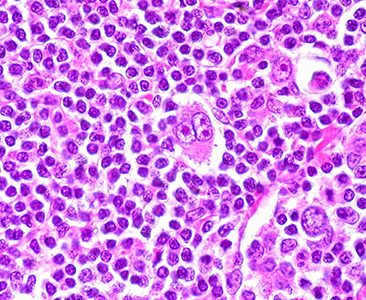

Certo, per uno che ha vinto una guerra contro un linfoma di Hodgkin al quarto stadio, sentire parlare di paura diventa quasi incredibile. Ma Simone, lui sì, è incredibile. E tutto gli è concesso.